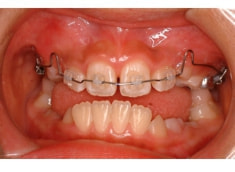

治療後(12ヶ月後)

検査時に予測した通り、骨格的下顎前突の要素はあまり発現しないで済みました。一期治療で反対咬合を解消しておいたことと、舌などの機能訓練に真面目に取り組んでいただけたことも良い要因であったと思います。

外科矯正も回避できて、さらに非抜歯で本格矯正を行うことができると診断し、現在2期治療中です。

下顎前突症例によくある顕著な顔面非対称もなく、幅径も良好な状態です。